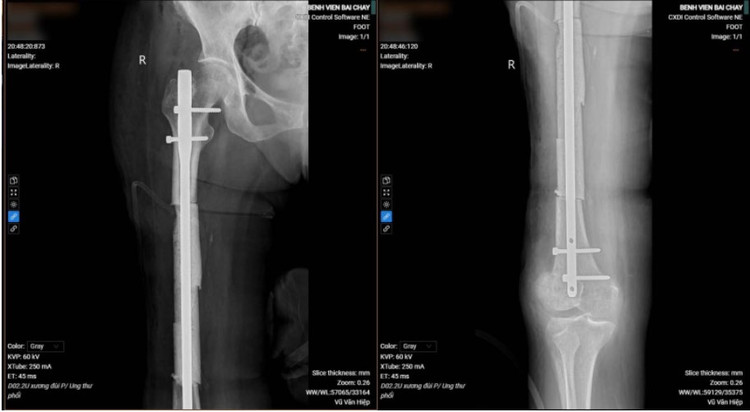

Bệnh nhân được xạ trị tích cực vùng não và xương đùi để tiêu diệt, ngăn chặn sự phát triển của tế bào ung thư, giảm đau, chống phù não. Tiếp đó, ca phẫu thuật phẫu thuật cắt bỏ đoạn u xương đùi do ung thư di căn, kết hợp xương, thay thế đoạn xương đùi khuyết bằng xi măng sinh học do bác sĩ Vũ Quang Nghĩa – Trưởng Khoa Chấn thương chỉnh hình thực hiện đã thành công giúp bệnh nhân phục hồi vận động.

![]() |

| Hình ảnh gãy xương, tiêu xương đùi phải của bệnh nhân trước và sau phẫu thuật - Ảnh BVCC |